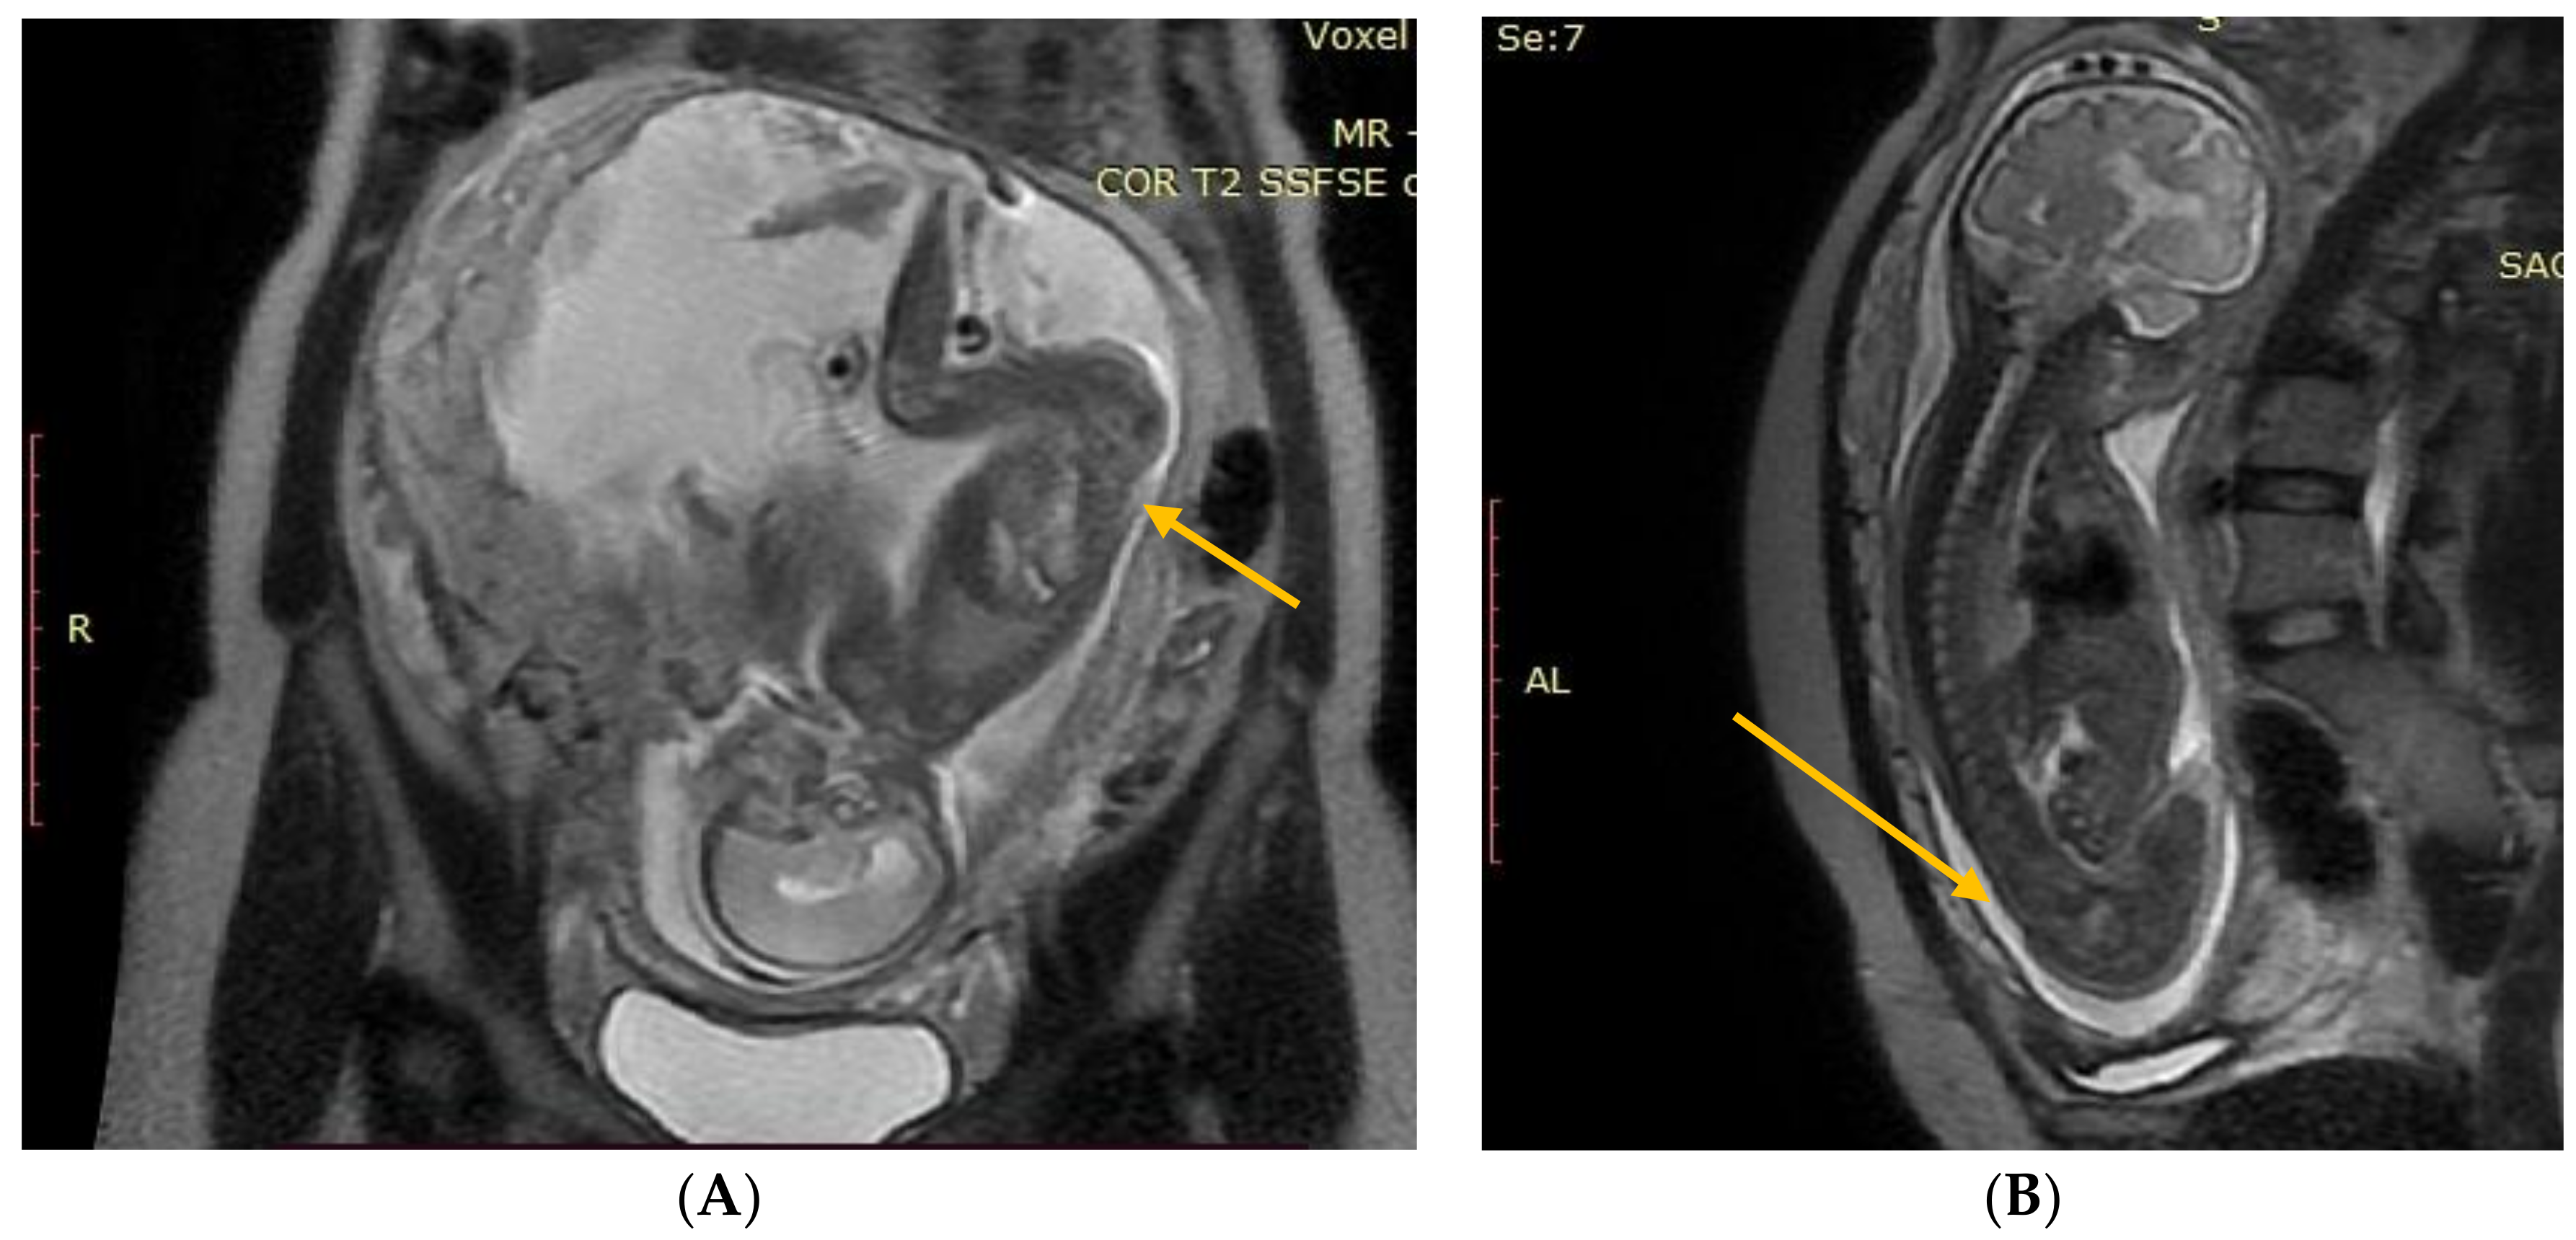

The results of the diagnostic MRI, performed between 21 and 24 weeks of gestation, were assessed (Figure 1 and Figure 2). During the test, the following parameters were evaluated: size and location of the spina bifida, presence and size of the hernia sack, size of the cerebral ventricles, structure of the posterior fossa, and severity of the Chiari malformation. Prenatal fetal NMR allowed to evaluate the development of the remaining fetal organs. Only fetuses with no other developmental defects were deemed eligible for the prenatal intervention. The NMR findings were compared to the perioperative imaging of the spinal split and hernia sack. After open fetal prenatal repair of spina bifida aperta, a follow-up ultrasound was performed at 2 weeks postoperatively, and repeated every 10–14 days. A follow-up fetal NMR was performed at 6–8 weeks postoperatively (Figure 1 and Figure 2).

Group I—12 (12.5%) patients with no hernia sack on diagnostic imaging and during surgical repair (Figure 1).

Figure 1. (A) Fetal NMR at 21 weeks of gestation. The arrow indicates the myeloschisis, with the area of contact between the split and the uterine wall. (B) Fetal NMR at 26 weeks of gestation (4 weeks after intrauterine myeloschisis repair); the arrow indicates the site after a three-layer reconstruction of spina bifida aperta.